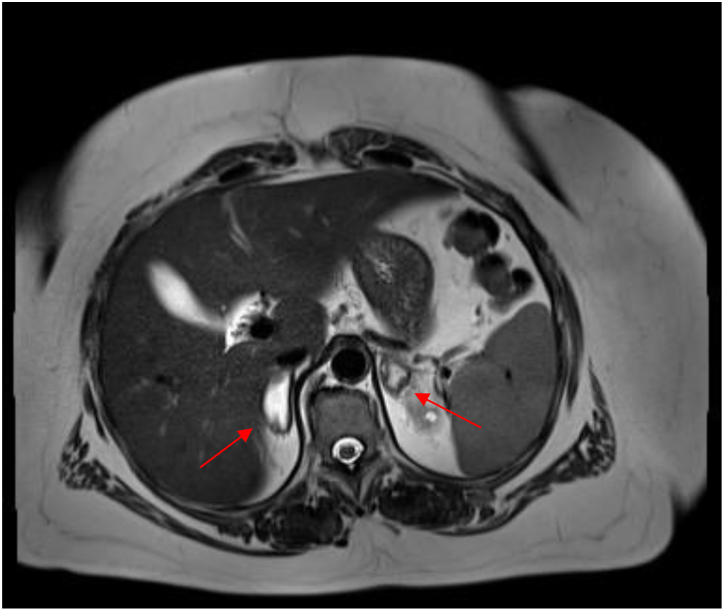

Summary: Adrenocortical insufficiency is defined as the clinical manifestation of chronic glucocorticoid and/or mineralocorticoid deficiency due to failure of the adrenal cortex. It may result in an adrenal crisis, which is a life-threatening disease; thus, prompt initiation of therapy with hydrocortisone is necessary. Symptoms such as hypotension, weight loss, or fatigue are not specific, which is why diagnosis is delayed in many cases. Our patient suffered from immune thrombocytopenia (ITP), an acquired thrombocytopenia caused by an autoimmune reaction against platelets and megakaryocytes. Primary ITP, in which no triggering cause can be identified, must be distinguished from secondary forms (e.g. in the context of systemic autoimmune diseases, lymphomas, or (rarely) by drugs). Patients may be asymptomatic at presentation or may present with a range of mild mucocutaneous to life-threatening bleeding. Here, we report on a 43-year-old woman who had developed adrenocortical insufficiency due to bilateral hemorrhage in the adrenal glands. Because of anticoagulation with phenprocoumon after pulmonary embolism and thrombocytopenia on the basis of ITP, the patient had an increased risk of bleeding. Due to the nonspecific and ambiguous symptoms of adrenocortical insufficiency, prompt diagnosis remains a challenge.